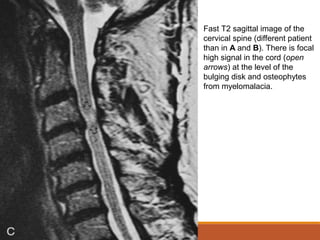

Fast T2 sagittal image of the

cervical spine (different patient

than in A and B). There is focal

high signal in the cord (open

arrows) at the level of the

bulging disk and osteophytes

from myelomalacia.